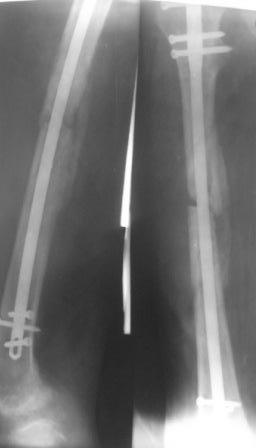

Больной явился 13.03.10г. (около100 дней п/о )  с двумя свищами на

бедре: один на уровне с/з бедра снаружи с гнойным отделяемым, второй

на уровне дистального метафиза бедра тоже снаружи со скудным отд.

Бедро не отечно, с признаками хрон. остеомиелита без обострений,

ходит с двумя костылями с частичной нагрузкой на лев.ногу, до сих пор

лечился у хирурга по м/жительства.

Уважаемые коллеги, может быть лучше использовать спейсер с

антибиотиками (но у нас нет костного цемента), или другие варианты

лечения? Р-снимок прилагается.